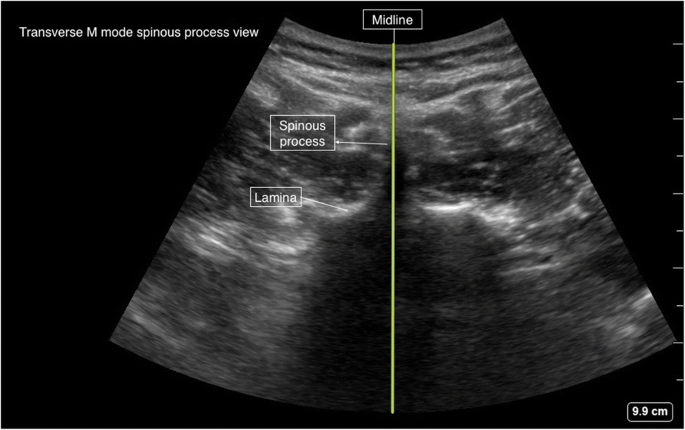

Transverse Spinous Process View

After identification of the appropriate interspace using the para-sagittal interlaminar view, the probe is turned 90° to obtain a transverse spinous process view (Fig. 12). The tip of the spinous process is identified as a white hyperechoic line with acoustic shadowing beneath it with a sloping lamina seen laterally (Fig. 13). This is the key view for the identification of midline (Fig. 5 probe position A) and the interspinous spaces between the consecutive spinous processes in obese patients. We recommend using M-mode line for determining the exact midline in this view (Fig. 14).

적절한 간격 공간을 파라사갈리탈 간층면 관점에서 식별한 후, 프로브를 90° 회전시켜 횡단 척추돌기 관점을 얻습니다(그림 12). 척추돌기의 끝부분은 아래에 음향 그림자가 있는 흰색 고반향선으로 식별되며, 측면에서 경사진 층판이 관찰됩니다(그림 13). 이 시야는 비만 환자에서 중간선(그림 5 프로브 위치 A) 및 연속된 척추돌기 사이의 척추돌기 간 공간을 식별하는 데 핵심적인 시야입니다. 이 시야에서 정확한 중간선을 결정하기 위해 M-모드 선을 사용하는 것을 권장합니다(그림 14).

The transducer is rotated 90° to obtain a transverse spinous process view at the desired interspace. The midline (vertical marking) is marked with the aid of the M-mode midline marker as shown in Figs. 13, 14, and 17.